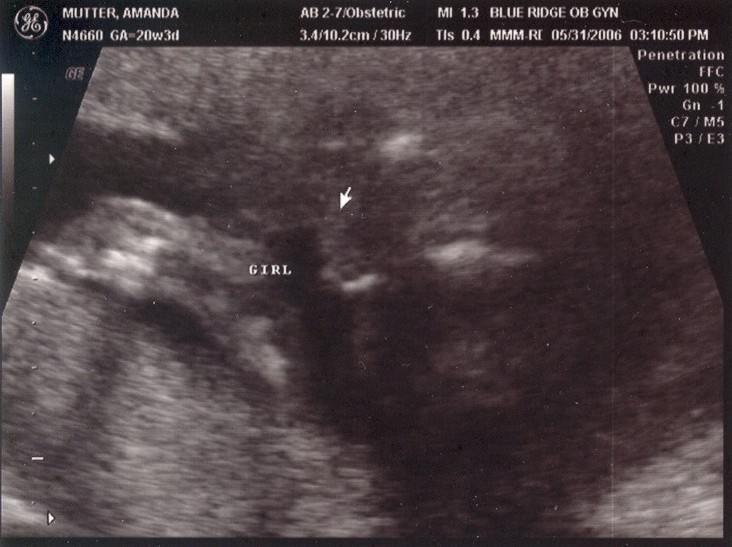

May 31, 2006: Diagnostic Ultrasound

OBs regularly do these to check if babies have all the right number of arms, brains, etc.

It's a girl! After getting this picture, my parents got to stop researching boys' names and circumcision.